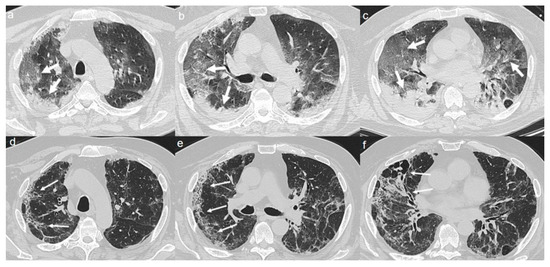

2.3. Case 3

On admission, chest CT showed a diffuse “crazy paving pattern” peripherally located in the upper and lower lobes (Figure 3a–c).

A CT at 4 months from the onset of symptoms revealed the bilateral persistence of a mixed pattern characterized by GGOs and fibrous streaks (Figure 3d–f).

Figure 3. (ac) CT shows a “crazy paving pattern” peripherally located in upper and lower lobes (arrows). (df) CT after 4 months from the onset of symptoms shows bilateral persistence of mixed pattern of GGOs (thin arrows in d) and fibrous streaks (thin arrows in e,f).